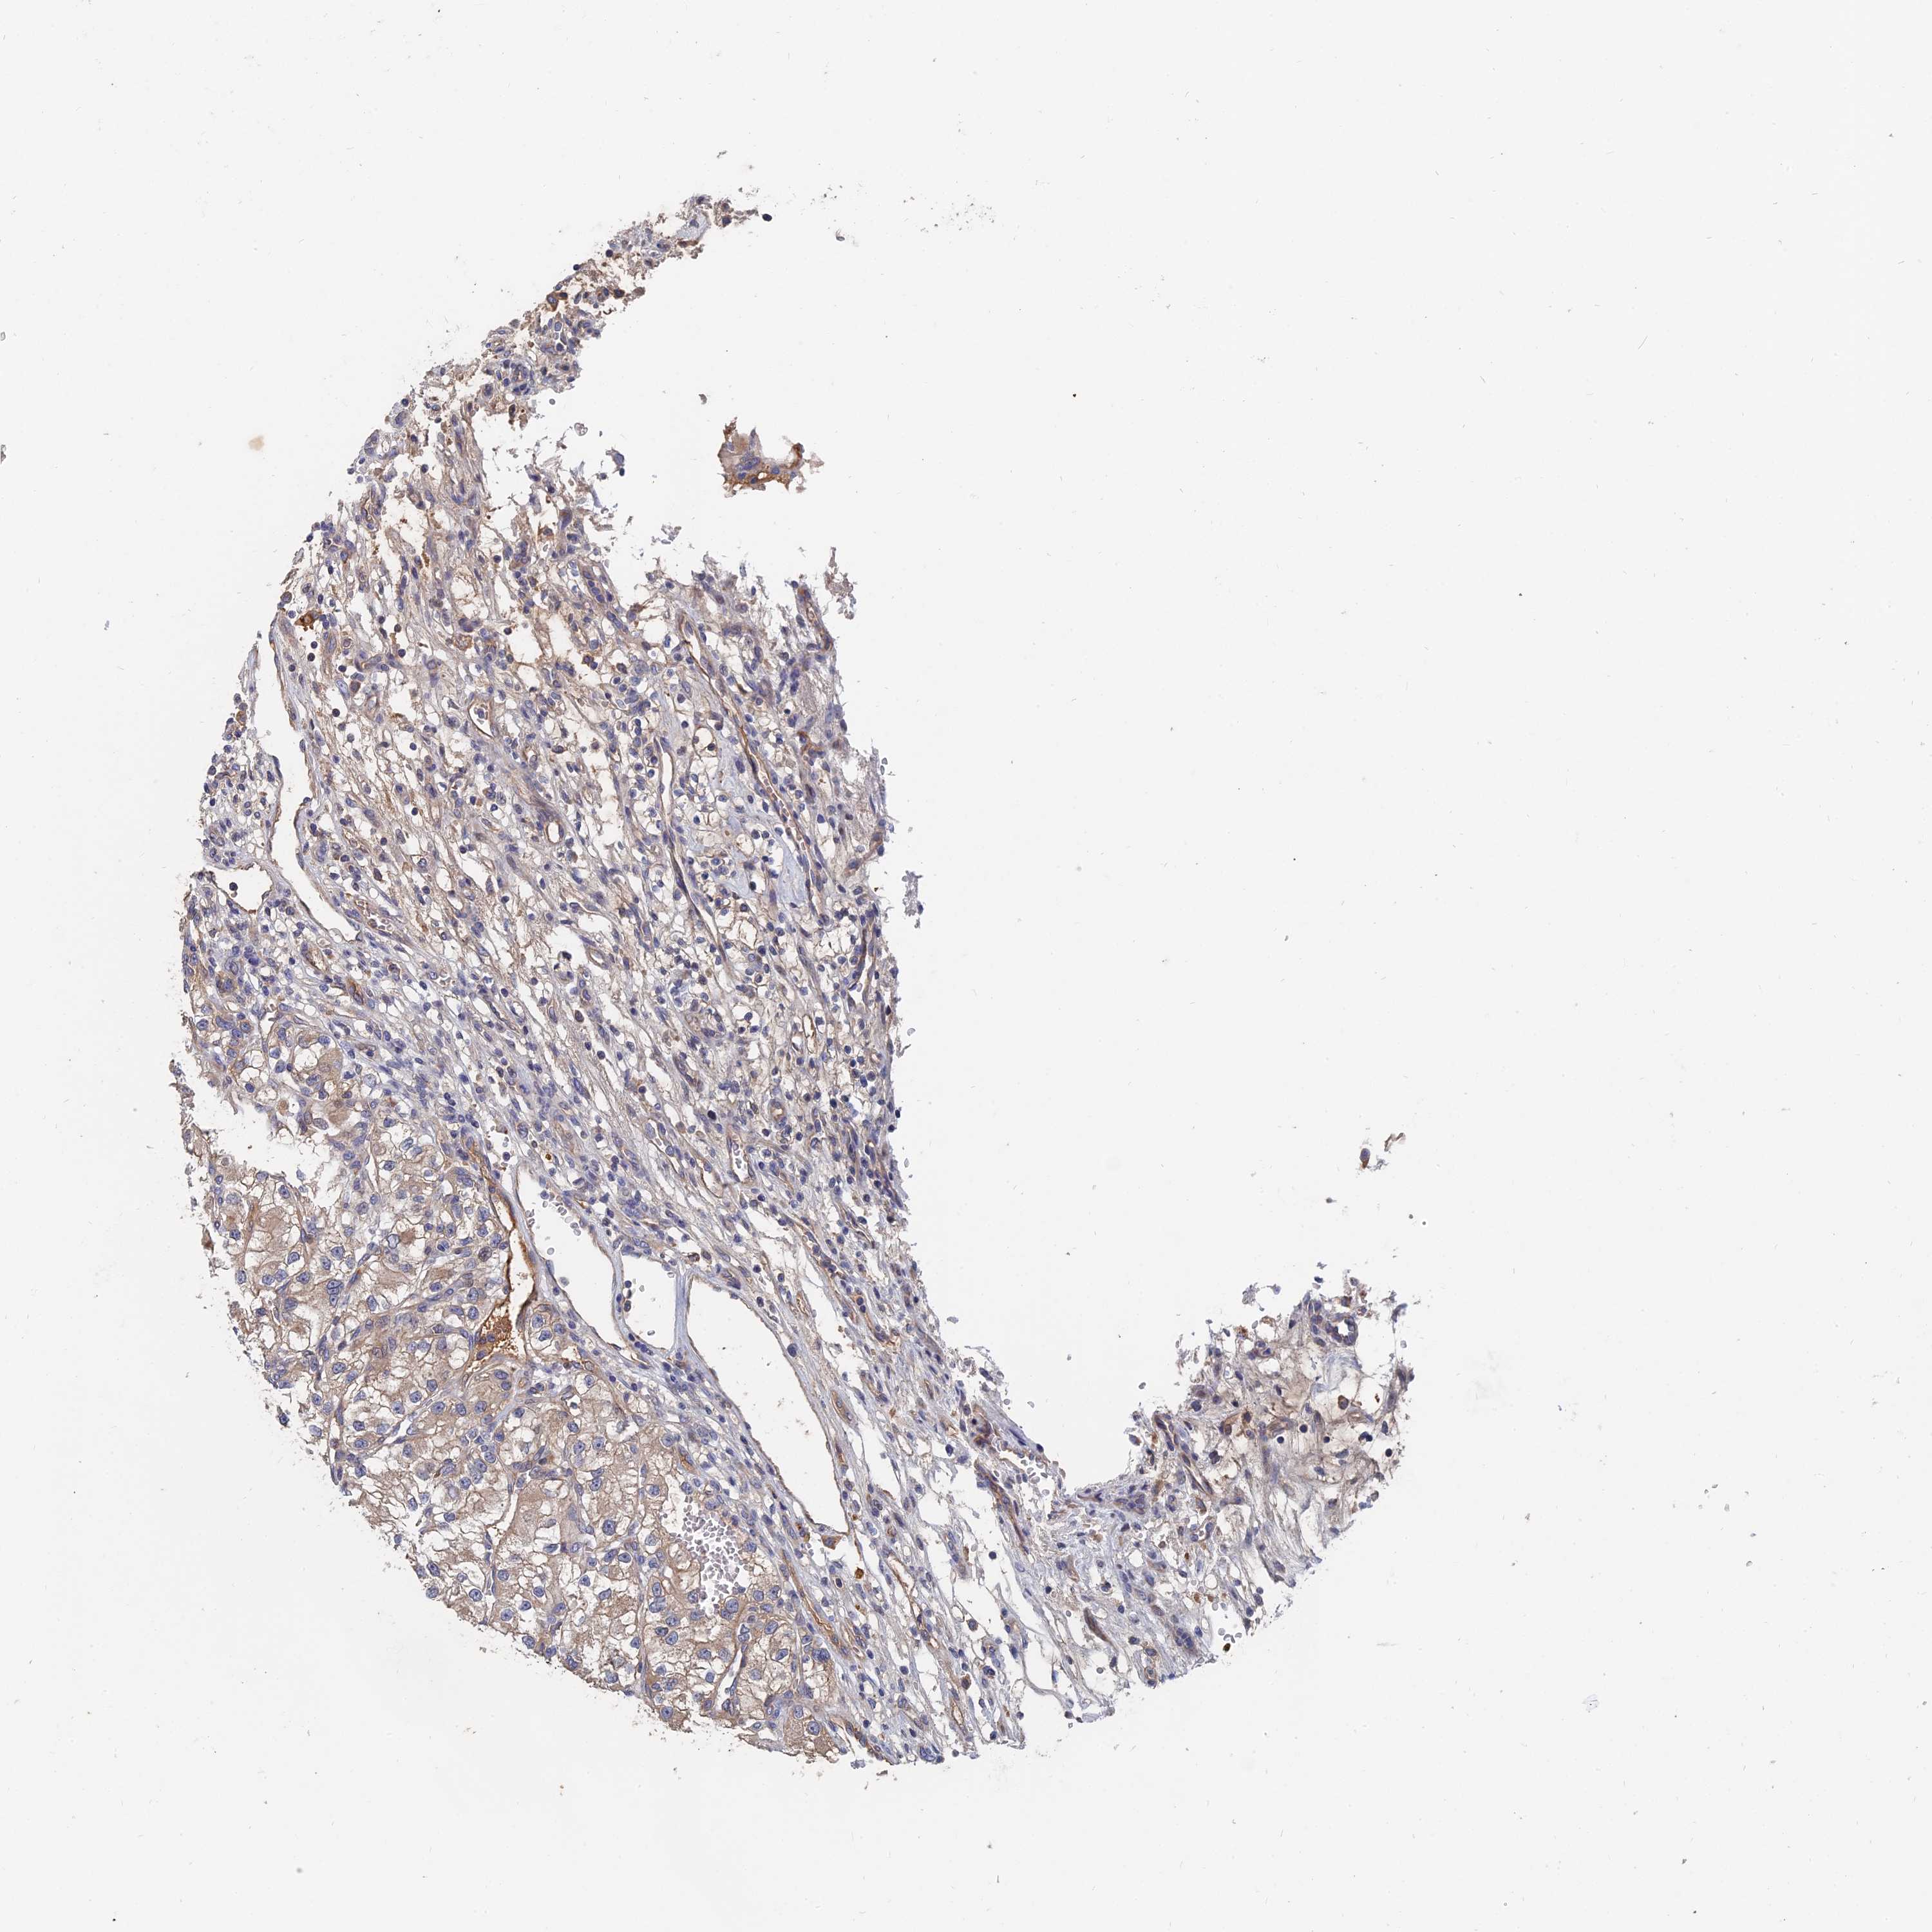

KIDNEY RENAL PAPILLARY CELL CARCINOMA (TCGA) - Interactive survival scatter ploti

The Survival Scatter plot shows the clinical status (i.e. dead or alive) for all individuals in the patient cohort, based on the same data that underlies the corresponding Kaplan-Meier plots. Patients that are alive at last time for follow-up are shown in blue and patients who have died during the study are shown in red.

The x-axis shows the expression levels (FPKM) of the investigated gene in the tumor tissue at the time of diagnosis. The y-axis shows the follow-up time after diagnosis (years). Both axes are complimented with kernel density curves demonstrating the data density over the axes. The top density plot shows the expression levels (FPKM) distribution among dead (red) and alive patients (blue). The right density plot shows the data density of the survived years of dead patients with high and low expression levels respectively, stratified using the cutoff indicated by the vertical dashed line through the Survival Scatter plot. This cutoff is automatically defined based on the FPKM cutoff that minimizes the p-score. The cutoff can be changed by dragging the vertical line or by entering a cutoff value in the square labeled "Current cut-off".

Under the Survival Scatter plot the p-score landscape (black curve; left axis) is shown together with dead median separation (red curve; right axis). Dead median separation is the difference in median mRNA expression between patients who have died with high and low expression, respectively. It is calculated as follows: median FPKM expression of dead patients with high expression - median FPKM expression of dead patients with low expression. This is intended to aid the user in visually exploring custom cutoffs and the associated p-scores and dead median separation.

Individual patient data is displayed and can be filtered by clicking on one or more of the category buttons on the top of the page. Categories describing expression level and patient information include: high, low, alive, dead, female, male and tumor stages. The scale of the x-axis can be toggled between linear and log-scale by clicking on the "x log" button. Mouse-over function shows TCGA ID, patient information and mRNA expression (FPKM) for each patient.

& Survival analysisi

Kaplan-Meier plots summarize results from analysis of correlation between mRNA expression level and patient survival. Patients were divided based on level of expression into one of the two groups "low" (under cut off) or "high" (over cut off). X-axis shows time for survival (years) and y-axis shows the probability of survival, where 1.0 corresponds to 100 percent.

SLC33A1 is not prognostic in Kidney Renal Papillary Cell Carcinoma (TCGA)